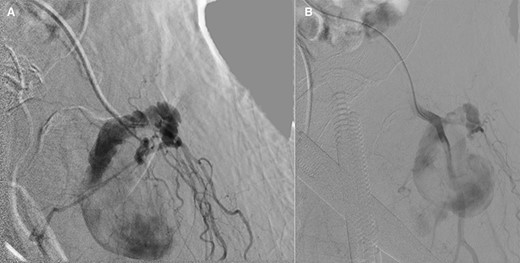

Vascular surgery was consulted and CT angiography demonstrated a large DFA pseudoaneurysm (Fig. 4A and B). Given her advanced years and comorbidities, a minimally invasive approach was recommended. The pseudoaneurysm was successfully embolized using numerous microcoils (Fig. 5). Completion angiography demonstrated complete occlusion of the pseudoaneurysm and patent superficial and DFA (Fig. 5). There were no immediate complications. After discussion with the patient, it was agreed that restarting her apixaban increased risk for her hematoma rebleeding and no anticoagulation was continued for stroke prevention.

(A and B): Frontal digitally subtracted angiography via a diagnostic catheter positioned in the proximal left DFA demonstrating a large pseudoaneurysm originating from a small DFA branch. The long, narrow and lobulated pseudoaneurysm neck can be see coursing along the cranial aspect of the pseudoaneurysm.

Postcoil embolization digitally subtracted angiography via a diagnostic catheter positioned in the left DFA demonstrating adequate embolization of the injured small DFA branch with complete exclusion of the pseudoaneurysm.